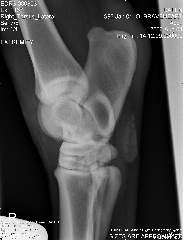

Hi Dr. O, after reading your article, I've added the lateral view of the stifle, can you tell if you can see if he has any of the following?

osteochonDrOsis dissecans

subchondral bone cyst

osteoarthritis

Stifle Lateral view

stifle lateral

Aileen, carefully reviewing an extensive list of radiographs like you have above for any abnormality even with the original set of full sized radiographs could take up to an hour and an hour more to write about. Reviewing these tiny pictures would be of no value at all. While I don't mind looking at the occasional radiograph the above is beyond the scope of this site.

If you want a second opinion on these I strongly recommend you send them to a certified veterinary radiologist, like you find at a university veterinary school, they could tell you more than I would be able to.

Surgeon says mild to moderate djd in hocks and stifle. His stiffness is much much better, not overall anymore, so I do think the hock injections helped.